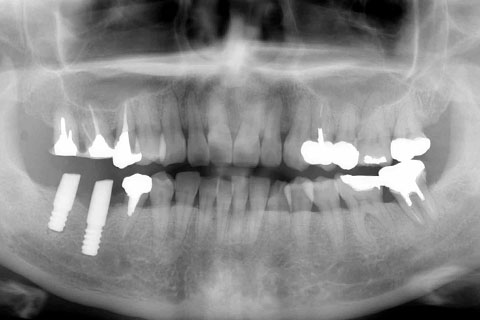

症例2

治療前

インプラント埋入時

治療後

- 年齢・性別

- 57歳男性

- 治療期間

- 3ヶ月

- 抜歯

- なし

- 治療費

- 154万円

- 備考

- 左上5.6.7 及び左下6.7欠損

- 治療内容

- 左上5.6.7と左下6.7欠損部にインプラント埋入

- 施術の副作用(リスク)

- オペによる知覚障害。インプラントによる歯肉炎。インプラント脱落。